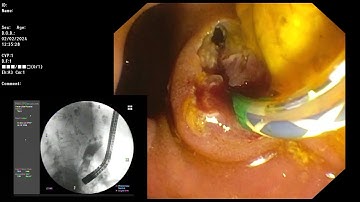

ERCP ; Old EST of intradiverticular type ampulla, passing stone.